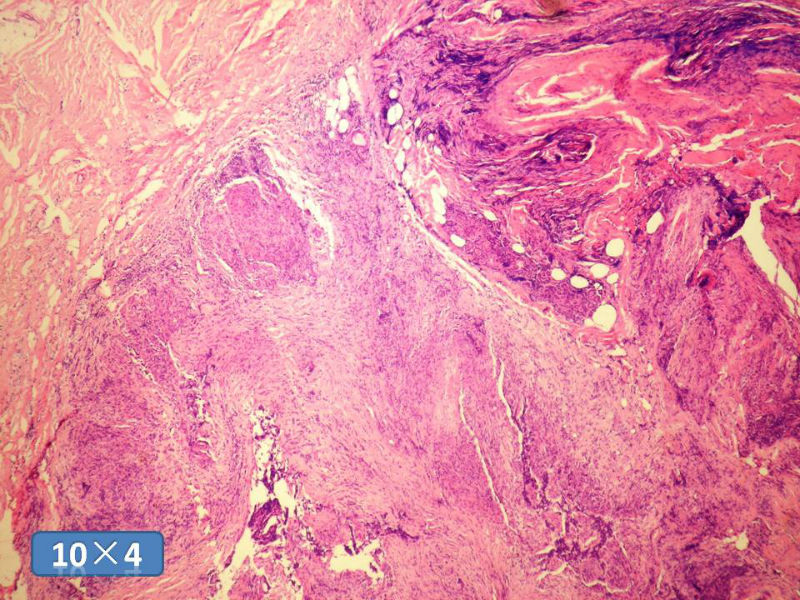

女性,50岁,乳腺肿物,冰冻切片(图1-25)

HE